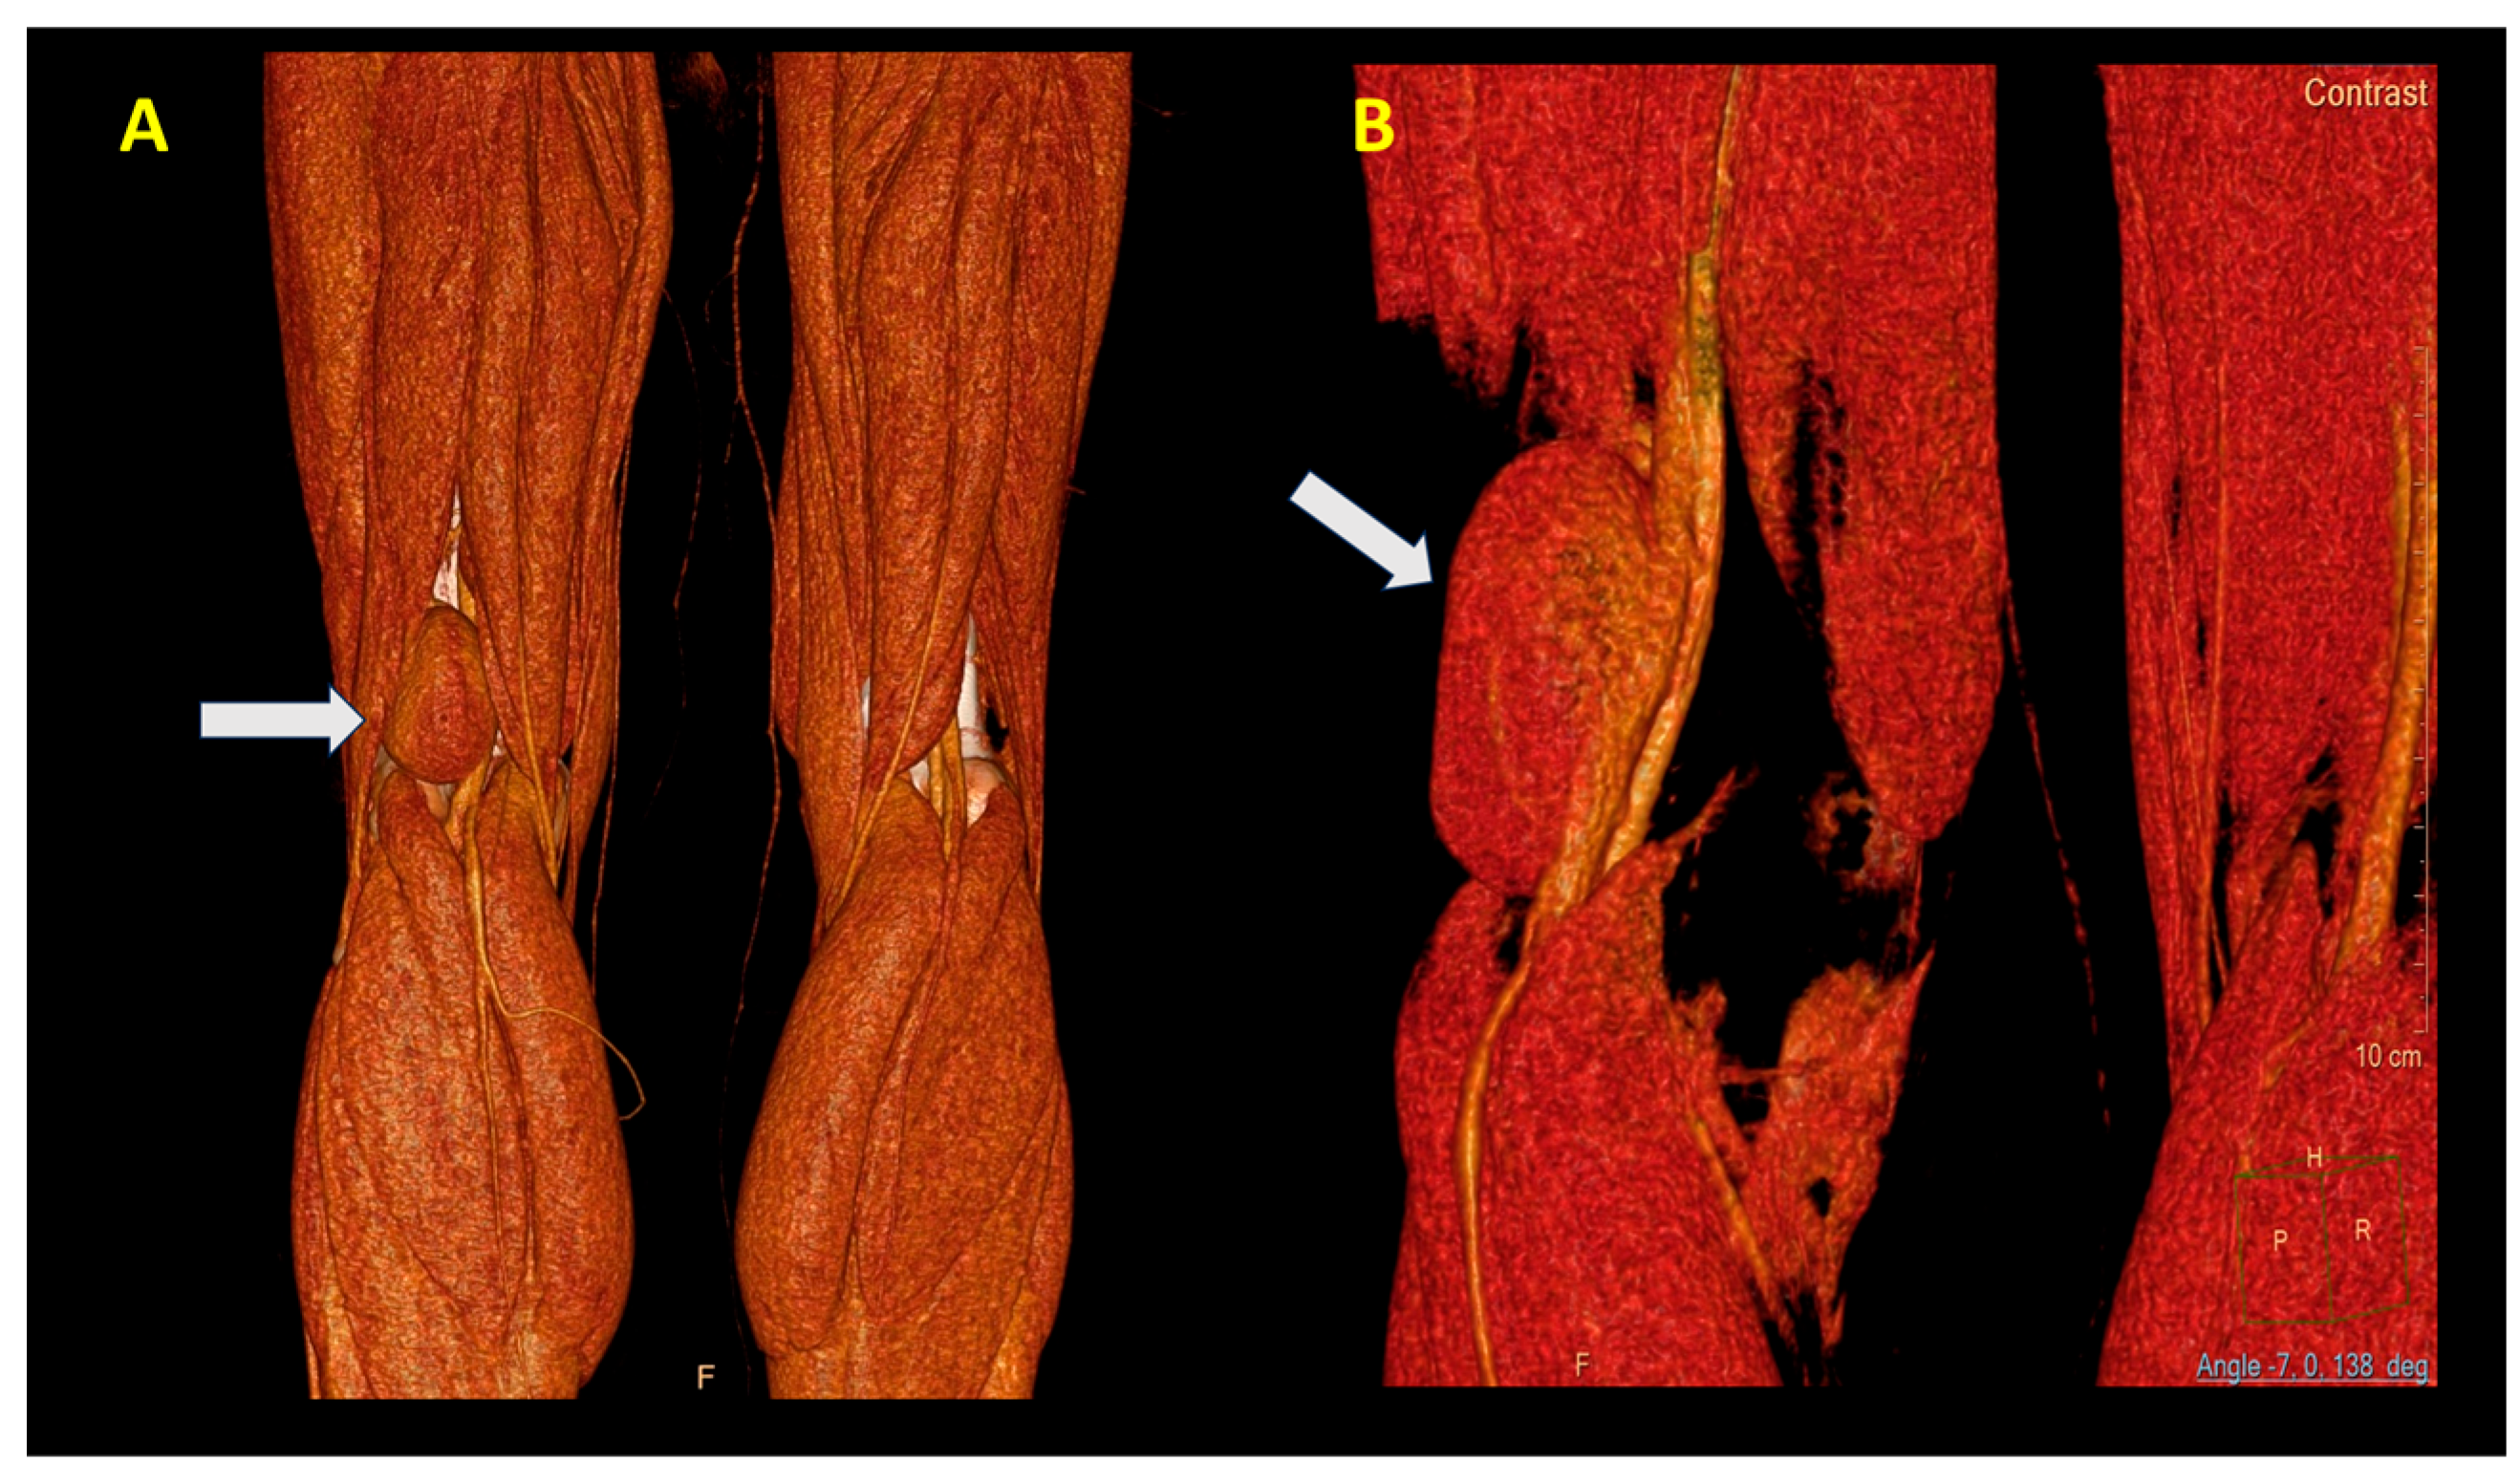

An angio CT was performed, which demonstrated the presence of an aneurysm with a communication between the popliteal vein and the cavity (Figure 3A,B).

Figure 3. View of the PVA (white arrow). (A) Posterior and (B) lateral view. Note the large dimensions (60 mm).